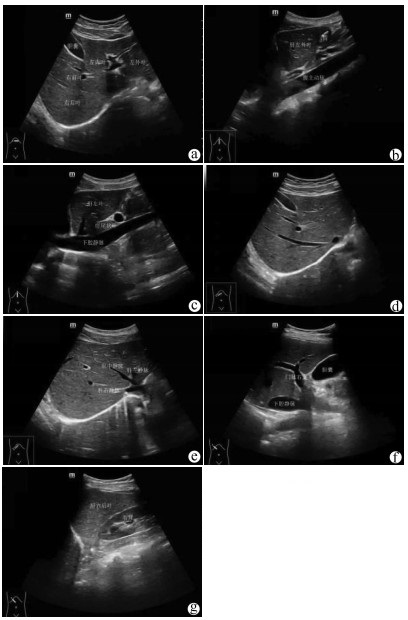

肝病超声诊断指南

中华医学会超声医学分会, 中国研究型医院学会肿瘤介入专业委员会, 国家卫生和健康委员会能力建设和继续教育中心超声医学专家委员会

2021, 37(8): 1770-1785. DOI: 10.3969/j.issn.1001-5256.2021.08.007

超声检查无创、实时、价廉,无辐射、便于反复进行,是最常用的肝脏影像学检查方法。近年来,超声检查新技术如超声造影、弹性成像发展迅速,可有效鉴别肝内占位性病变性质、评估肝纤维化和门静脉高压程度以及监测肝病治疗效果,在临床肝病及其介入治疗中发挥重要诊断价值。本指南规范了肝病多模态超声技术(灰阶超声、彩色多普勒超声、超声造影、弹性超声)检查的仪器调置、患者准备及医生检查方法;对肝脏弥漫性病变(炎性病变、纤维化、硬化)、多种占位性病变及肝病介入操作的多模态超声技术诊断标准进行了定义和规范,同时推荐了超声监测周期及肝脏疾病超声诊断报告书写规范。